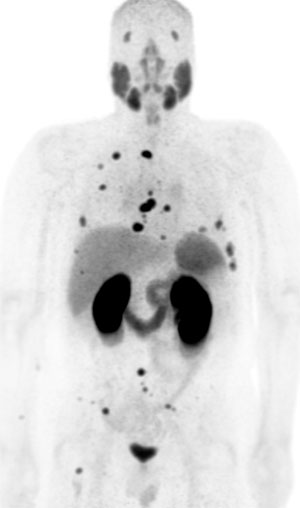

This retrospective review of patients with PSMA-PET imaging looked at 125 patients following RP with low PSA (≤2.0 ng/mL) and assessed if the recurrent disease was within standard radiation target volumes.  They compared patient and clinical variables between men with recurrences covered by standard salvage radiation fields and those with recurrences outside of standard fields. Overall, they found that 68Ga-PSMA-11 PET detects disease in a majority of patients with PSA ≤2.0 following RP. Nearly one-third of men had PSMA-avid disease that would be missed by standard radiation fields. Overall, they concluded that 68Ga-PSMA-11 PET is an imaging modality that can dramatically impact the design and use of post-RP salvage radiotherapy. The results were published in the July 2019 issue of Urology.